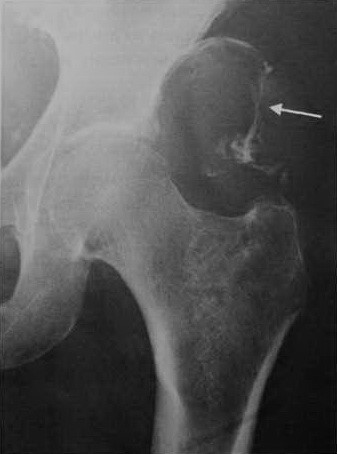

Больше похоже на рецидив ГКО, возможно - малигнизация, или изначально - злокачественная ГКО. Только гистологически, без рентгеновских методов, трудно дифференцировать с остеосаркомой (неча давать ответы в чате )))

Анна,теперь гаданий меньше не стало. "Злокачественная опухоль мезехимального генеза (веретеноклеточная саркома)" помимо вышеперечисленных включает еще, к примеру, злокачественную фиброзную гистиоцитому. Для ЗФГ, кстати, характерны и рецидивы, и метастазы в л/узлы. А вот для остеосаркомы мтс в л/узлы как раз не очень характерны.

Зло в костях почти все - саркома. Тем не менее, гистологический тип важен для выбора лечения. Хотя тут все плохо. И спрогрессировало быстро. Температурная реакция может быть симптомом отдаленного метастазирования. По органам не смотрели: легкие, печень?